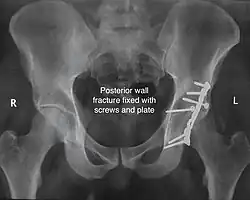

Posterior column and wall fracture as seen on 3D CT -

Posterior column and wall fixed using screws and plates